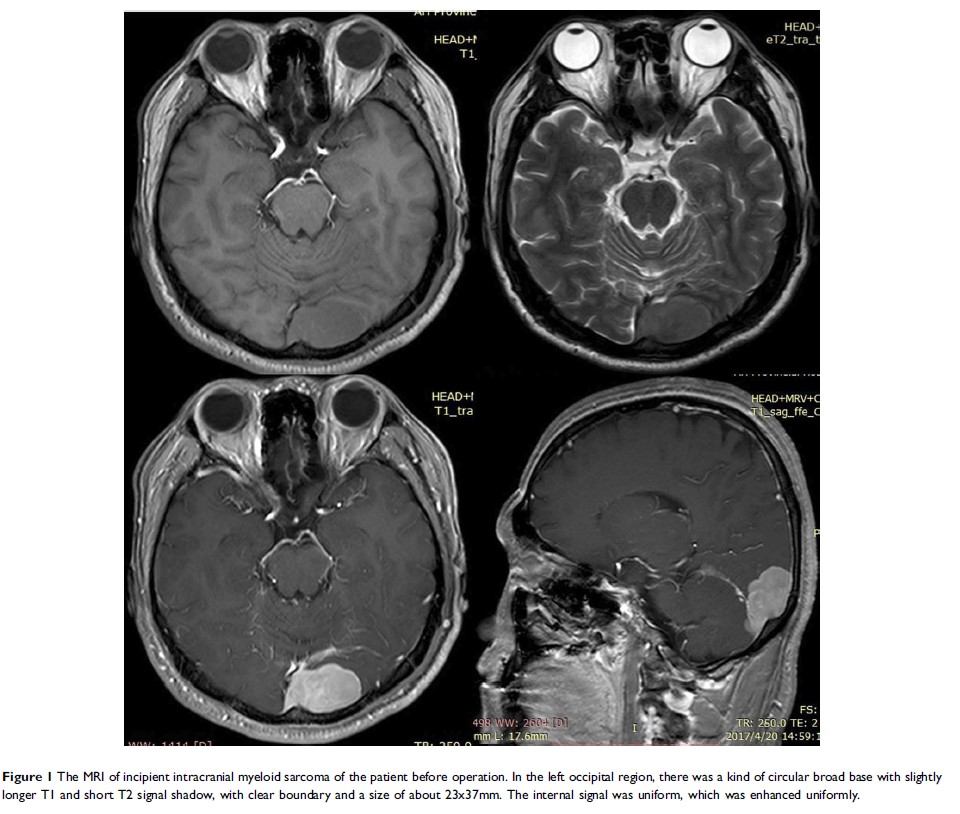

紧急化学疗法成功救治了由颅内髓系肉瘤引起的急性颅内高压症濒临死亡的病人